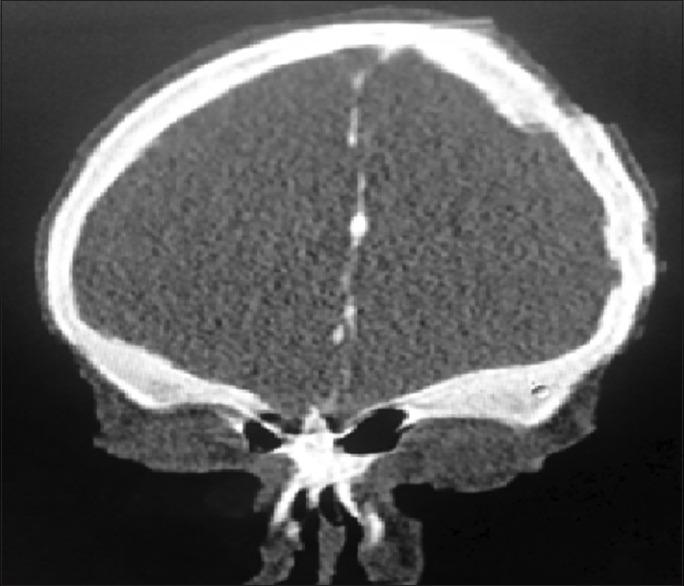

Gorlin-Goltz syndrome (GGS) is a rare autosomal dominant disorder with multisystemic involvement. It is characterized by the triad of multiple baso-cellular epitheliomas, odontogenic keratocysts (OKC) in the jaws and skeletal anomalies. Later, it was found that calcification of falx is also highly specific. We present radiological findings in case series of two cases, one with multiple OKC, calcified falx, skin lesions, and fibrous dysplasia of sphenoid and second with multiple OKC, calcified falx, vertebral anomaly and medulloblastoma.

戈林-戈尔茨综合征(GGS)是一种罕见的常染色体显性疾病,累及多系统。其特征为三联征,即多发性基底细胞上皮瘤、颌骨牙源性角化囊肿(OKC)和骨骼异常。后来发现,大脑镰钙化也具有高度特异性。我们展示了两个病例系列的影像学表现,一例有多发性OKC、大脑镰钙化、皮肤病变和蝶骨纤维发育不良,另一例有多发性OKC、大脑镰钙化、椎体异常和髓母细胞瘤。